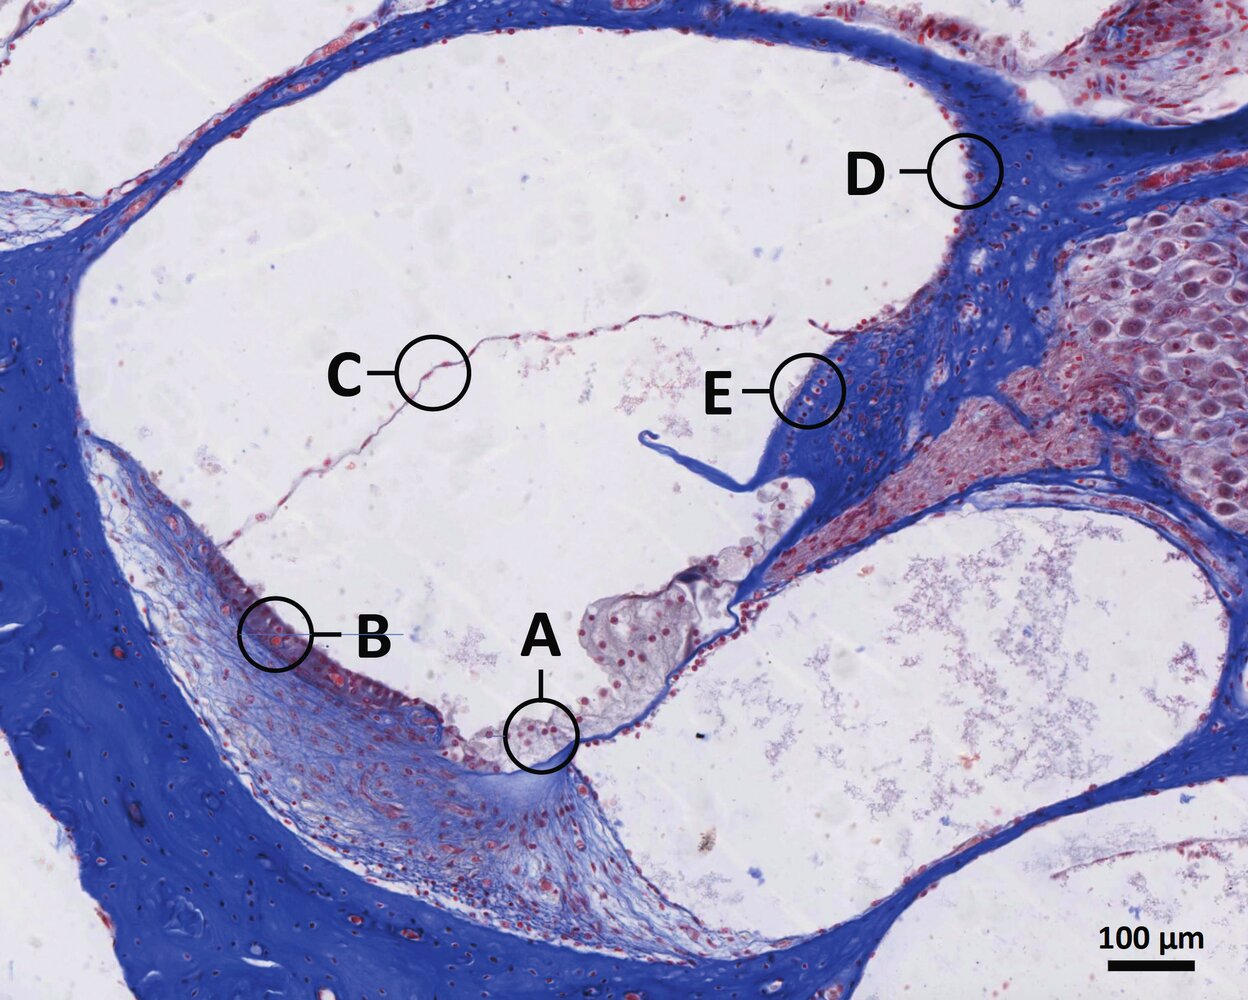

13. The image shows a section of a histological slide of an organ.

Where is the largest portion of this organ located?

A. Posterior to the masseter muscle (M. masseter)

B. Caudal (below) to the mylohyoid muscle (M. mylohyoideus)

C. Between the palatoglossal arch and palatopharyngeal arch (Arcus palatoglossus and Arcus palatopharyngeus)

D. Caudal to the thyroid cartilage (Cartilago thyroidea)

E. Secondarily retroperitoneal between the descending part of the duodenum and the spleen